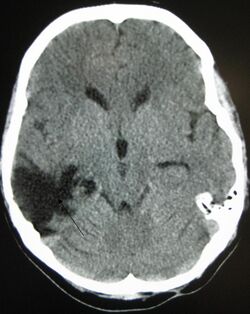

Brain trauma CT.jpg

CT scan showing cerebral contusions, hemorrhage within the hemispheres, and subdural hematoma. There is also displaced skull fracture of left transverse parietal and temporal bones.[2]